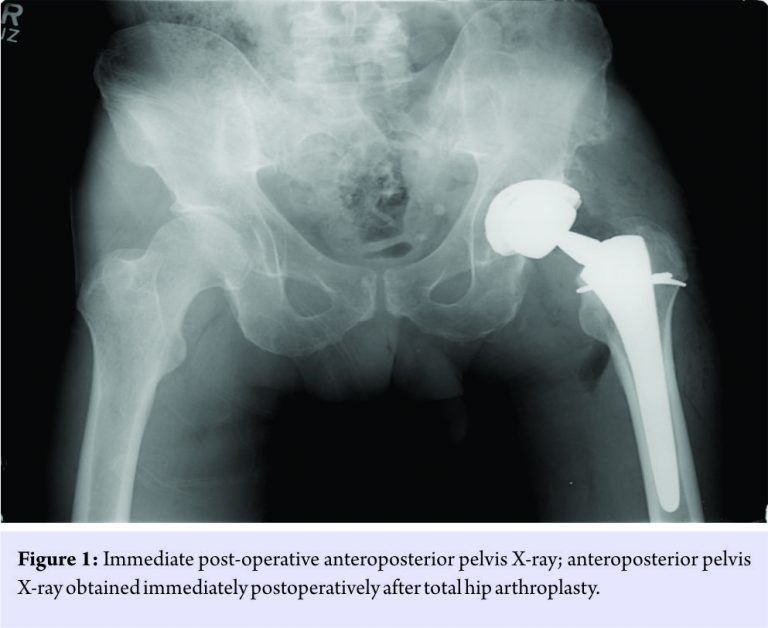

A 63-year-old male, whose medical history was notable only for mild left hip dysplasia, initially presented to our clinic with a 2-year history of progressively worsening left groin pain. Before his pain was intensifying, he routinely engaged in high-level fitness and recreational activities, including jogging and mountain hiking. In spite of non-operative treatments including nonsteroidal anti-inflammatory medications, activity restriction, and several intra-articular corticosteroid injections, his pain progressed and began interfering with routine activities of daily living. On exam, he was healthy appearing, with a body mass index of 23.5 kg/m2, and an antalgic gait. He demonstrated full strength with hip flexion and abduction, with a range of motion from 0 to 120° of flexion, 20° of internal rotation (which was painful), 30° of external rotation, and 30° of abduction. Radiographs and magnetic resonance imaging (MRI) demonstrated partial uncovering of the femoral head with end-stage degenerative changes of the left hip. Spine pathology was excluded. He, therefore, elected to undergo THA. At THA, acetabular components included a non-cemented hydroxyapatite-coated Ti acetabular shell with modular cross-linked polyethylene (Stryker Trident PSL cup, 54 mm diameter; X3 0° liner), a ceramic modular head (Stryker Biolox Delta, 40 mm diameter, +0 mm Ti trunnion adapter sleeve), a non-cemented hydroxyapatite-coated Ti femoral stem (Stryker Rejuvenate SPT stem, size #10), and a CoCr modular neck (Stryker Rejuvenate, V40 trunnion taper, 34 mm length, 0° version, 127° angle neck). A calcar cable was placed due to a limited vertical calcar fracture, and full weight-bearing was permitted. After routine post-operative care, including peri-operative antibiotics, deep vein thrombosis prophylaxis, and physical therapy, the patient was discharged home 2 days postoperatively after an uneventful hospitalization. An anteroposterior pelvis X-ray obtained in the post-anesthesia care unit is shown in Fig. 1